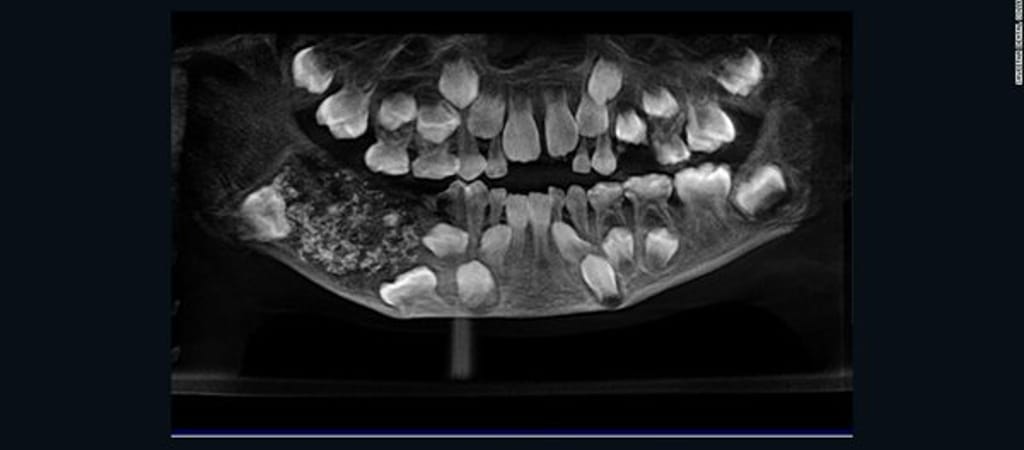

Kórházba vittek egy hétéves fiút Indiában, mert nagyon fájt az állkapcsa. Aztán amikor megröntgenezték, az orvosok alig hitték el, amit láttak: a gyerek alsó állkapcsa teli volt fogakkal, összesen 526 darab nőtt – írta a CNN.

A legkisebb fog egytized milliméteres volt, a legnagyobb is csak 15 milliméteres. De mindegyik szabályos fog volt, saját gyökérrel, koronával – magyarázták az orvosok. A fogakat eltávolították – természetesen azokat leszámítva, amelyeknek valóban ott volt a helyük -, a fiú pedig már jól van, és ki is engedték a kórházból.